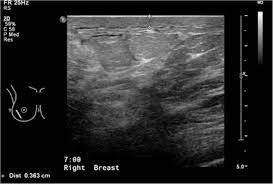

It's called inflammatory because that's how it looks. Any area that does not look like normal tissue is a possible cause for concern. Inflammatory breast cancer, also known as carcinomatous mastitis, t4d, or pev 2 or 3, is the only real therapeutic emergency in breast oncology, given the high risk of metastasis, the reason for the most unfavourable prognosis of all breast cancers.it must consequently be diagnosed rapidly, and imaging examinations must in no case delay therapeutic management. Because ibc grows quickly, it is usually found at a locally advanced stage, meaning that cancer cells have spread into nearby breast tissue or lymph nodes. A breast ultrasound is a scan that uses penetrating sound waves that do not affect or damage the tissue and cannot be heard by humans. Ultrasound is useful for looking at some breast changes, such as lumps (especially those that can be felt but not seen on a mammogram) or changes in women with dense breast tissue. As these inflammatory breast cancer picture shows, the texture of the breast may change and appear to look dimpled or ridged, like an orange peel. Their differences, however, lie in their enhancement.

These tubes, which are hollow, allow lymph fluid to drain out of the breast. The problem is that inflammatory breast cancer can look very much like mastitis early on, and is often diagnosed only after a woman has been treated first for mastitis (often with no improvement in symptoms). Kathleen ruddy inflammatory breast cancer accounts for approximately 5% of all cases of invasive breast cancer in the united states. Inflammatory breast cancer is often misdiagnosed because it is so rare, and is difficult to treat because it is particularly aggressive. A small red spot that looks very much like an insect bite or rash can be an early sign of ibc. Because ibc grows quickly, it is usually found at a locally advanced stage, meaning that cancer cells have spread into nearby breast tissue or lymph nodes. Googled and freaking out about ibc. The woman who has inflammatory breast cancer has breast cancer that's red and inflamed, with an angry look to the breast cancer, he says. Online says it develops suddenly. However, these signs and symptoms are most often associated with benign breast conditions. Inflammatory breast cancer (ibc) is rare, making up about 2 to 4 percent of breast cancer cases. Other ultrasound findings that suggest breast cancer include: The breast tissue deflects these waves causing echoes, which a computer uses to paint a picture of what's going on inside the breast tissue (no radiation is involved).

Rapid onset of symptoms (redness, swelling, warmth, itching, skin thickening) are hallmarks of the disease. You can imagine my fear when a red area appeared on my chest. Early warning signs of inflammatory breast cancer along with images of inflammatory breast cancer are mentioned below. However, inflammatory breast cancers are more likely to show solid mass lesions. The aim of this study was to evaluate the features of inflammatory breast carcinoma (ibc) on mri compared with mammography and ultrasound and to better define the role of mri in patients with this aggressive disease. I need some knowledge about ibc. My last breast ultrasound was december. I know imaging doesn't show ibc.